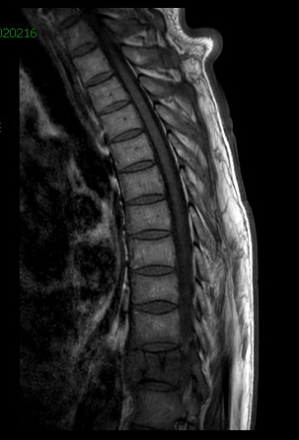

经过慎重考虑,老李决定返乡,并慕名来到我院就诊。脊柱外三科主任陈海龙看到老李的脊柱DR片后,顿感情况不妙,胸11椎体高度降低,椎体骨质及右侧附件结构严重破坏,幸运的是老李目前没有神经损伤症状,否则严重的话可造成双下肢截瘫。陈主任安排医师为老李紧急办理了住院手续,一边叮嘱他绝对卧床,一边加快各项相关检查。结合他的CT及MRI等影像资料显示,结果不过容乐观,不出所料,胸11肿瘤毫无疑问,而后穿刺活检的病理结果再次证实了医生的判断:骨巨细胞瘤。但幸运的是,经过全面彻底排查,未见肿瘤转移,那么此时此刻对老李来讲,完整彻底地切除肿瘤,是最优的选择。